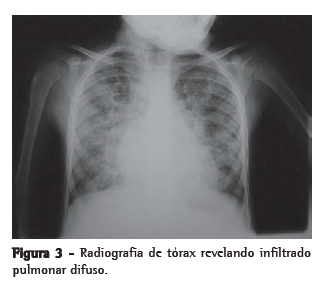

Para ilustrar a utilização do líquido de LBA no diagnóstico de afecções pulmonares, exibe-se a seguir a imagem radiológica (Figura 3) e do líquido de LBA (Figura 4) que auxiliaram no diagnóstico de hemossiderose pulmonar em uma criança com histórico de hemoptise e anemia ferropriva.

Embora a biópsia pulmonar seja considerada o padrão ouro, a presença de hemosiderin-laden macrophages (HLM, macrófagos contendo hemossiderina) no líquido de LBA é considerada crucial para o diagnóstico de hemossiderose pulmonar idiopática diante de achados sugestivos da doença, como hemoptise, infiltrado intersticial em radiografia de tórax e anemia ferropriva.(37,38) Um grupo de autores(38) revisou dados do perfil celular de líquido de LBA coletado de crianças para correlacionar a presença de HLM e hemossiderose e concluiu que a presença de 36% de HLM entre o total de macrófagos apresenta 100% de sensibilidade e 96% de especificidade para o diagnóstico da doença.